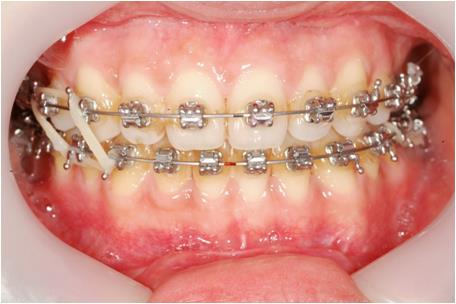

°ñ°ÝÀûÀÎ ¹®Á¦¸¦ µ¿¹ÝÇÏÁö ¾ÊÀº »óÅÂÀÎ °æ¿ì Ä¡¿À» °í¸£°Ô ÇÏ°í ±³ÇÕÀ» È®¸³Çϱâ À§ÇÑ Æ÷°ýÀûÀÎ Ä¡¿±³Á¤(±×¸²1)Àº Ä¡·á¹æ¹ý¿¡ µû¶ó Å©°Ô ºñ¹ßÄ¡ ±³Á¤(Ä¡¾Æ¸¦ ¹ßÄ¡ÇÏÁö ¾Ê°í ±³Á¤ÇÏ´Â ¹æ¹ý)°ú ¹ßÄ¡ ±³Á¤(Ä¡¾Æ¸¦ ¹ßÄ¡ÇÏ¿© ±³Á¤ÇÏ´Â ¹æ¹ý)À¸·Î ºÐ·ùÇÒ ¼ö ÀÖ½À´Ï´Ù. Åë»óÀûÀ¸·Î °ø°£ÀÌ ¸¹ÀÌ ºÎÁ·Çϰųª ÀÔÀÌ µ¹ÃâµÈ °æ¿ì ¹ßÄ¡ ±³Á¤ÀÇ ´ë»óÀÌ µÈ´Ù°í ÇÒ ¼ö ÀÖÀ¸¸ç ±â°£Àº ³À̵µ¿Í Ä¡¾ÆÀÇ ¹è¿»óÅ¿¡ µû¶ó ´Ù¼Ò Â÷À̰¡ ÀÖ°ÚÀ¸³ª ÃÖ¼Ò 1³â ÀÌ»óÀÇ ½Ã°£ÀÌ ÇÊ¿äÇÕ´Ï´Ù. ¹ßÄ¡ ±³Á¤ÀÇ °æ¿ì À̸¦ °í¸£°Ô ¹è¿ÇÑ ¼ö ¹ßÄ¡°ø°£À» Æó¼âÇÏ´Â ±â°£ÀÌ Ãß°¡ÀûÀ¸·Î ÇÊ¿äÇÏ°Ô µÇ¹Ç·Î ÀϹÝÀûÀ¸·Î 2³â ³»¿ÜÀÇ ±â°£ÀÌ ÇÊ¿äÇÕ´Ï´Ù. ¼ºÀå±â ȯÀÚÀÇ °æ¿ì´Â »ý¸®Àû ¹ÝÀÀÀÌ ¼ºÀκ¸´Ù Ȱ¹ßÇÏ¿© Ä¡¾ÆÀÇ À̵¿ ¶ÇÇÑ ºü¸£°Ô ÀϾ¹Ç·Î ºñ½ÁÇÑ Áõ·Ê¶ó°í ÇÏ´õ¶óµµ ¼ºÀκ¸´Ù´Â ±â°£ÀÌ Âª°Ô ³¡³ª´Â °æ¿ì°¡ ÀϹÝÀûÀÔ´Ï´Ù.

| | ±×¸²1 |